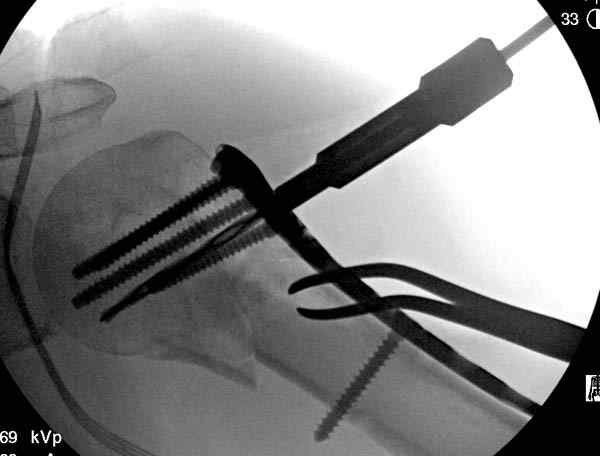

Для облегчения рентгенологического контроля во время операции мы применяем полусидячее, так называемое положение “beach chair” на операционном столе. Наши столы позволяют поднять ножной конец до необходимой высоты, только надо усадить больного к ножному концу стола.

Ошибки встречаются тогда, когда удовлетворяются только одной проекцией рентгена.

Здесь пример открытой репозиции 57 летнего с переломом плеча (1,2) смещение обнаружено на интероперационном снимке. При нормальной прямой проекция (3) угловое смещение обнаружили в аксиальной проекции (4)

После устранения смещения пластина установлена выше (5,6,7) и финальные снимки (8,9,10)

Подбор импланта тоже имеет значение, например многие импланты направлены для фиксации перелома без учета ротаторной манжетки. Предпочтительными являются низко сидящие полиаксиальные пластины, где верхние шурупы можно проводить под углом в 120 градусов. (11)

Пластина от Synthes или ее копии (надеюсь простят критику друзья из Деоста) считаются трудным из-за обширности доступа, особенно при установке верхне-заднего шурупа, где доступ надо расширять в верхнем отделе до ротаторной манжетки. Верхне сидящие импланты предназначены для проведения опоры (buttress) за бугристость плеча, но тогда приходится сталкиваться с подакромиальным импинжментом.